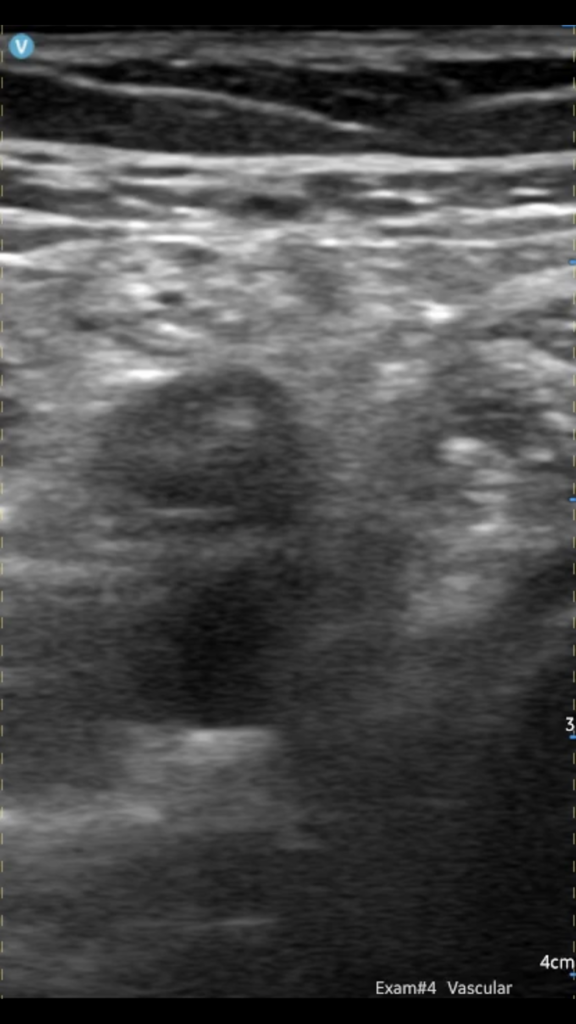

when i was last in ER, ER residents were taught how to do this study.One of my partner’s PAs grabbed me as I was coming in this morning and asked if I would take a look at a patient she was worried had a DVT. I told her about the ultrasound yesterday and she was very interested in potential uses for it. Told the patient I’m not a sonographer and he would need to have a real study performed regardless, but apparently his PCP had ordered it a few days before and he hadn’t been contacted to schedule yet. Started with the popliteal fossa, and sure enough, he had a DVT! Sent him to the ER and they did a formal study that confirmed it.

View attachment 345091